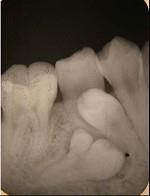

融合牙是 ( )

- D.两牙牙本质相连

D